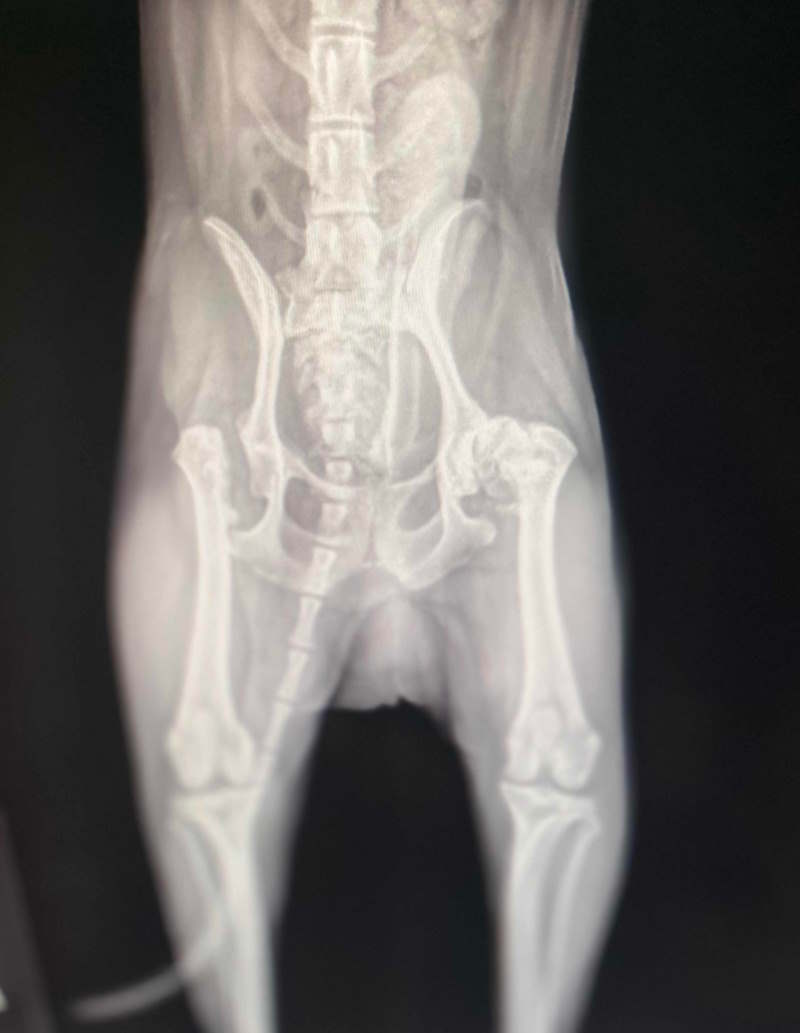

x-ray of a dog with a femoral head ostectomy This is Ketchikan's X-ray before his second Femoral Head Ostectomy. He underwent surgery on his right side about 4 years ago and is getting ready for surgery on his left side.